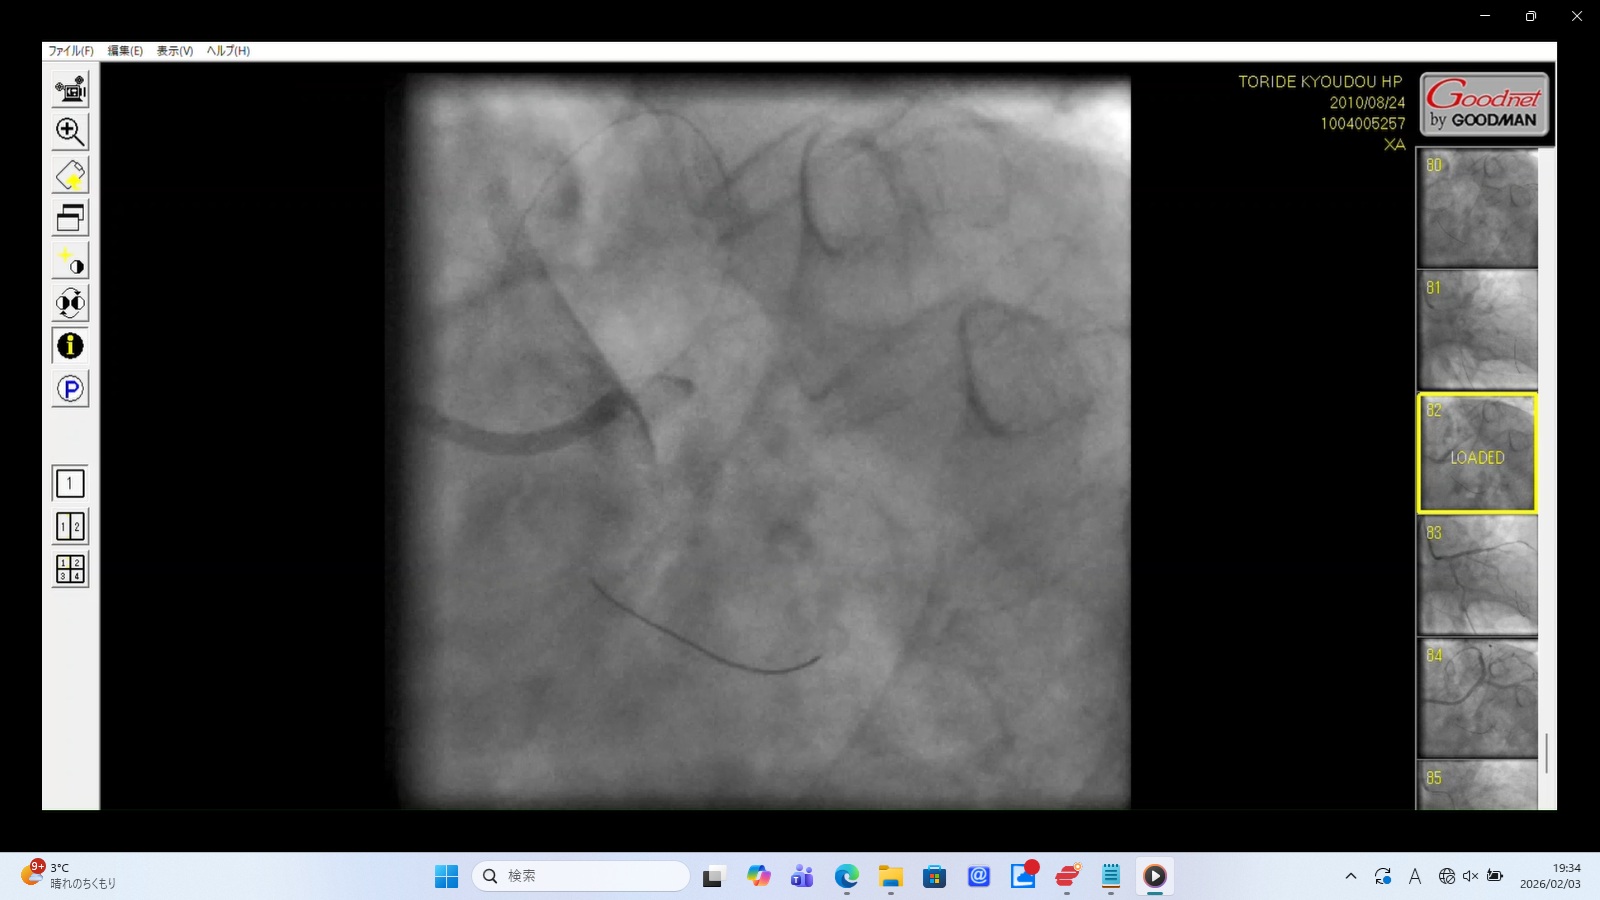

22時35分に開始され、右橈骨動脈にガイドワイヤーを挿入して手技が開始されたが、 冠動脈にアプローチできず、右大腿動脈から挿入された。その間、アプローチが失敗した時間帯のPCI画像が 存在せず、ここで大事故を起こした証拠であるこの間の画像が抜き取られた可能性が疑われる。 PCIは3時間と長時間を要し、その間の放射線被曝量も人体に深刻な影響を与えるほど大量であった。 PCIの動画を確認すると左冠動脈主幹部解離・損傷・閉塞、左冠動脈前下行枝解離・穿孔、 左回旋枝への血栓閉塞、ステント様人工物の血管外落下など多数の致命的な大事故が認められた。 救命のためには心臓血管外科での開胸手術が必要のはずであったが、PCI終了後、医師は遺族に対して「治療は無事成功した」としてこの大事故を隠蔽し、心臓血管外科への手配をせずに放置し談笑していた。

また23:15~23:25頃、「血栓吸引」との記載があるが、その時間帯を含む23:08~23:26の18分間の動画が存在しない。 その後の動画では左冠動脈主幹部が解離・損傷。そのリアルタイムの証拠が抜き取られた可能性がある。 - 8月24日~25日:カテーテル手技の大事故(冠動脈損傷・閉塞・穿孔)

左前下行枝解離・穿孔、左冠動脈主幹部解離・損傷・完全閉塞、ステント様人工物の血管外脱落などの所見あり。 術者の岩井利之医師は「治療は成功した」と偽り、これらの大事故・大損傷を隠蔽した。救命のためには心臓血管外科での緊急手術が必要な状態であったはずだが、医師らはその手配をせず放置した。